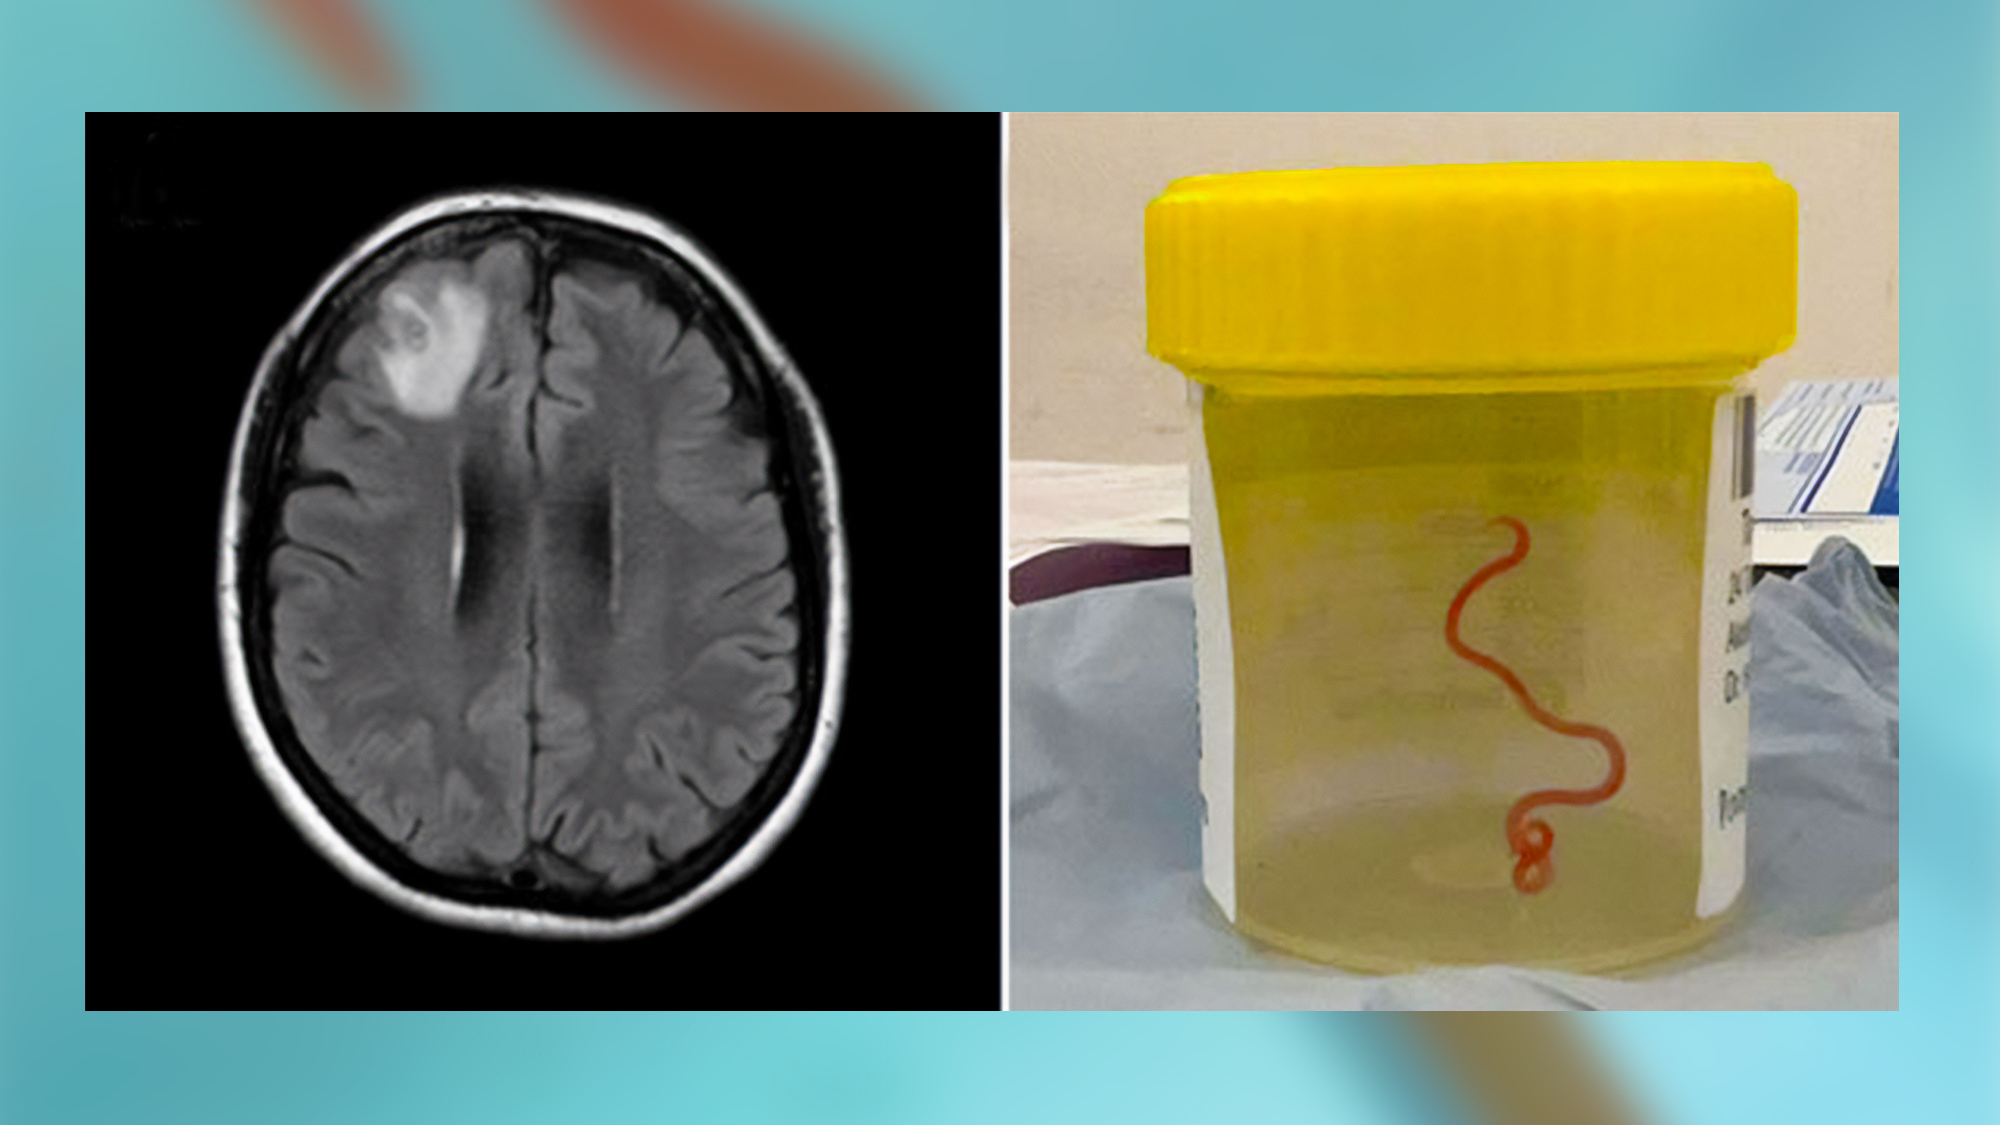

A magnetic resonance image of the patient’s brain by fluid-attenuated inversion recovery showing an enhancing right frontal lobe lesion (left). A live third-stage larval form of Ophidascaris robertsi removed from the patient’s right frontal lobe (right).

A magnetic resonance image of the patient’s brain by fluid-attenuated inversion recovery showing an enhancing right frontal lobe lesion (left). A live third-stage larval form of Ophidascaris robertsi removed from the patient’s right frontal lobe (right). Hossain M/Kennedy KJ/Wilson HL

The patient was first admitted to her local hospital in late January 2021 after experiencing three weeks of diarrhea and abdominal pain, followed by dry cough, night sweats, and fever. By June 2022, she was also experiencing forgetfulness and depression, and was referred to Canberra Hospital. While there, she underwent brain surgery when an MRI revealed some abnormalities.

Neurosurgeon Hari Priya Bandi was performing a biopsy when she used forceps to pull the parasite out of the woman’s brain. She immediately contacted Canberra Hospital infectious diseases physician Sanjaya Senanayake, saying “Oh my god, you wouldn’t believe what I just found in this lady’s brain—and it’s alive and wriggling,” Bandi said, according to The Guardian.